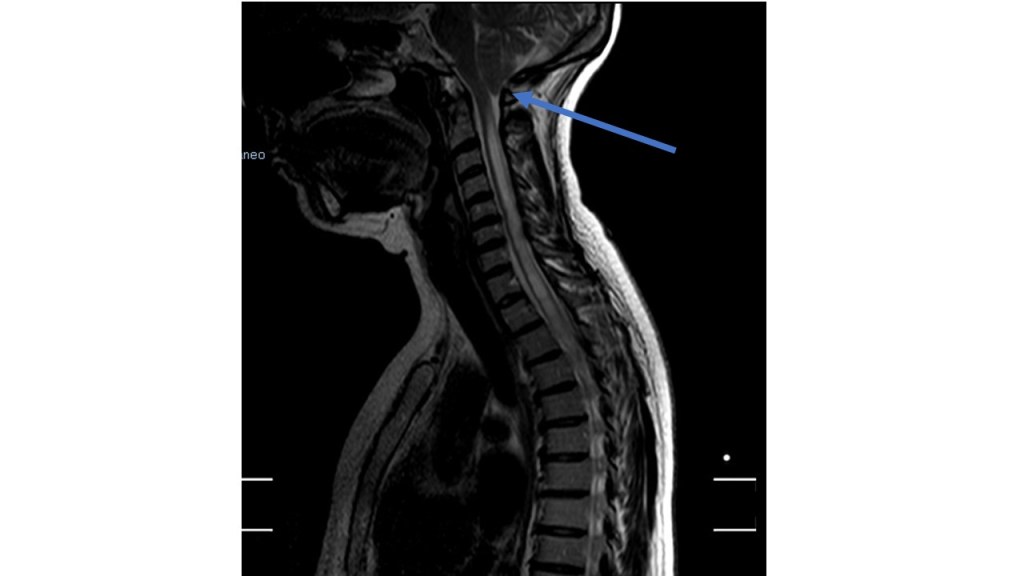

-La malformación de Chiari I se define por la presencia de una alteración de la circulación de líquido cefalorraquídeo a través del foramen magno. Puede ser congénita o adquirida. Clásicamente se caracterizaba por la presencia de una herniación de las amígdalas cerebelosoas mayor de 5 mm a través del foramen magno, si bien en la actualidad se considera que este criterio no es ni suficiente ni necesario para su diagnóstico. Va a estar asociada a siringomielia (aumento de líquido cefalorraquídeo en el interior del cordón medular) entre un 30-70% de los casos. La hidrocefalia puede estar presente en entre el 7-9% de los casos con Chiari I

-Se habla además de Chiari zero (Chiari 0) en aquellos casos en los que existe una siringomielia que presenta adecuada respuesta a la descompresión quirúrgica de la fosa posterior pese a no acompañarse de herniación amigdalar.